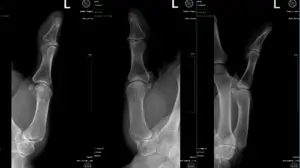

Live surgery tuesday: 3rd & 4th Phalanx ORIF

Live surgery tuesday at Badia Hand to shoulder center: Officer Ramirez 3rd & 4th phalanx ORIF Read more about the surgical treatment for unstable mallet finger.